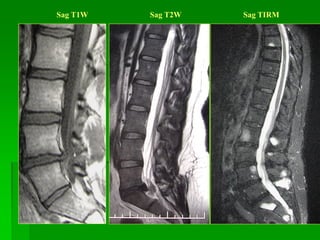

Sag T1W Sag T2W Sag TIRM

Sag T1W SagT2W Sag TIRM